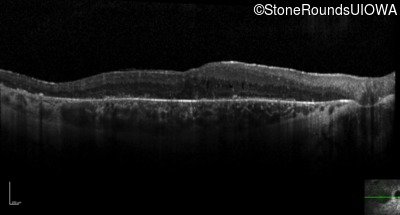

Optical Coherence Tomography - Left - 20/50 -1

Exemplar / OCT Stack

OCT Stack